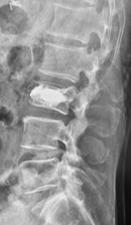

椎体形成術(VP、BKP、VBS)および後方・後側方脊椎固定術

対象となる疾患は、脊椎圧迫骨折や転移性脊椎腫瘍による病的骨折などです。椎体形成術でセメントや人工骨を注入して、骨折を人工的に接合します。椎体形成術のみでは固定性が弱い場合や骨脆弱性が強いには、スクリューなどを用いて脊椎を安定化させます。原則、手術翌日より軟性もしくは硬性のコルセットを装着し、起立・歩行を開始します。

-

(左)第12胸椎および第1腰椎の骨粗鬆症性椎体骨折を認めます。(中)MRIでは第1腰椎に大きな骨欠損を認め、骨折が難治性で不安定であることを示しています。(右)第1腰椎に椎体形成術を施行し、さらに骨が脆かったため、頭尾側にスクリューを挿入して固定しています。